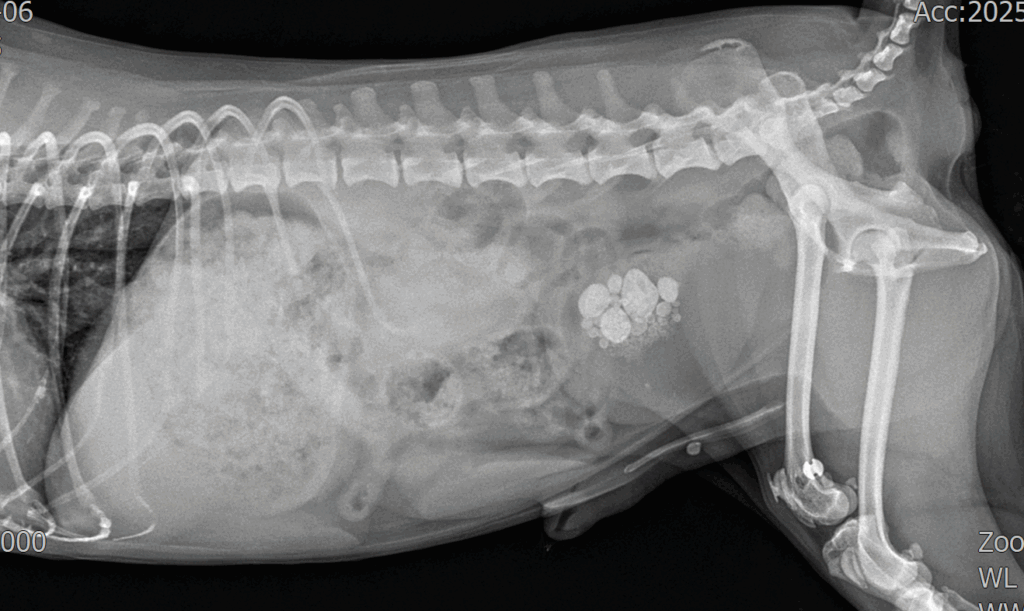

응급 진료 후 방사선(X-ray) 촬영을 진행한 결과, 요도 내에 결석이 걸려 있는 것이 확인되었으며 방광 내부에도 다량의 결석이 존재했습니다.

내원 시 방사선사진 / 출처: 24시온숲동물의료센터